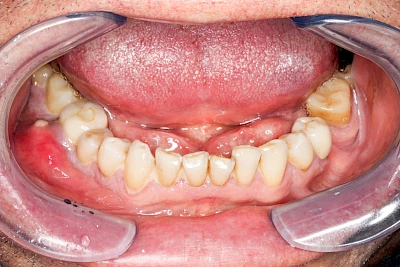

Ist zunächst nur das Zahnfleisch von der Entzündung betroffen, spricht man von Gingivitis. Später, wenn auch der Knochen um die Zähne herum entzündet ist, spricht man von einer Parodontitis. Bei der Parodontitis wird der Knochen nach und nach abgebaut und das Zahnfleisch zieht sich zurück. Die Zahnhälse und Zahnwurzeloberflächen liegen mehr und mehr frei. Die Zähne werden zunehmend lockerer und fallen schließlich aus.

Gingivitis & Parodontitis: Stadien